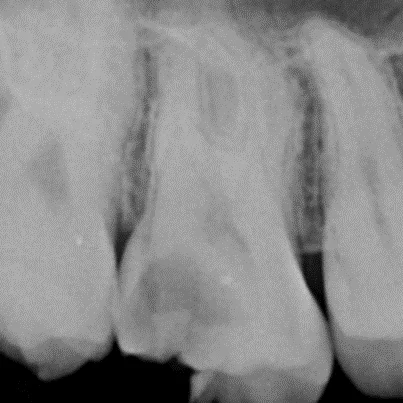

- 深層蛀牙導致牙髓受感染。

這些情況可能引起牙髓(牙齒內部的神經與血管)發炎或壞死,治療目的是去除感染組織,恢復牙齒功能。

- 診斷與評估:牙醫透過X光片和臨床檢查確認受影響的牙髓狀態。